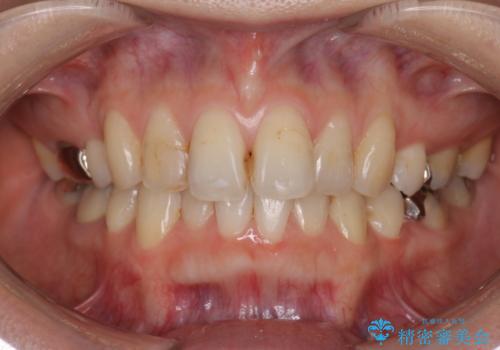

- 銀歯が気になるためやり替えたいとのことで来院されました。

セラミックインレーで治療を行いました。

口の中にチラつく銀歯は適合の良いセラミックインレーでやり替えることで綺麗にやり替えることができます。